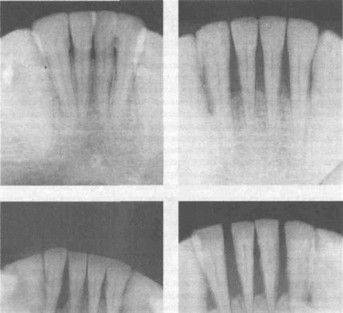

Катаральное воспаление десен

Патологический карман

Рентгенологический снимок – резорбция челюсти

Атрофическое воспаление десен

Оголение передней группы зубов

Резорбция челюсти